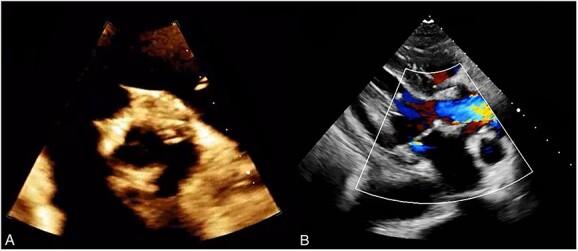

Rare but potentially fatal, brucellosis prosthetic valve endocarditis is a complication of brucellosis caused by Brucella species. The symptoms of brucellosis can be nonspecific, making the diagnosis challenging. Osteoarticular involvement is the most common complication of brucellosis. Mortality from brucellosis is low except for endocarditis and involvement of the central nervous system. The diagnosis is based on laboratory tests and clinical manifestations. Serological tests are preferred, as culture methods can be unreliable. A 59-year-old woman presented with gastrointestinal bleeding, fever, anorexia and malaise. She had a history of aortic valve replacement with a mechanical prosthesis for severe bicuspid aortic stenosis. Investigations revealed a multiloculated aortic root abscess encircling the prosthetic valve. She was diagnosed with brucella endocarditis, treated with antibiotics and underwent cardiac surgery. Her symptoms improved following the surgery. Brucellosis prosthetic valve endocarditis is a rare presentation of this disease.

摘要

布鲁氏菌性人工瓣膜心内膜炎虽罕见但可能致命,是由布鲁氏菌属引起的布鲁氏菌病的一种并发症。布鲁氏菌病的症状可能不具特异性,这使得诊断颇具挑战性。骨关节受累是布鲁氏菌病最常见的并发症。除心内膜炎和中枢神经系统受累外,布鲁氏菌病的死亡率较低。诊断基于实验室检查和临床表现。血清学检测更为可取,因为培养方法可能不可靠。一名59岁女性出现胃肠道出血、发热、厌食和全身不适。她有因严重二叶式主动脉瓣狭窄接受机械瓣膜主动脉瓣置换术的病史。检查发现围绕人工瓣膜的多房性主动脉根部脓肿。她被诊断为布鲁氏菌性心内膜炎,接受了抗生素治疗并接受了心脏手术。术后她的症状有所改善。布鲁氏菌性人工瓣膜心内膜炎是这种疾病的罕见表现。